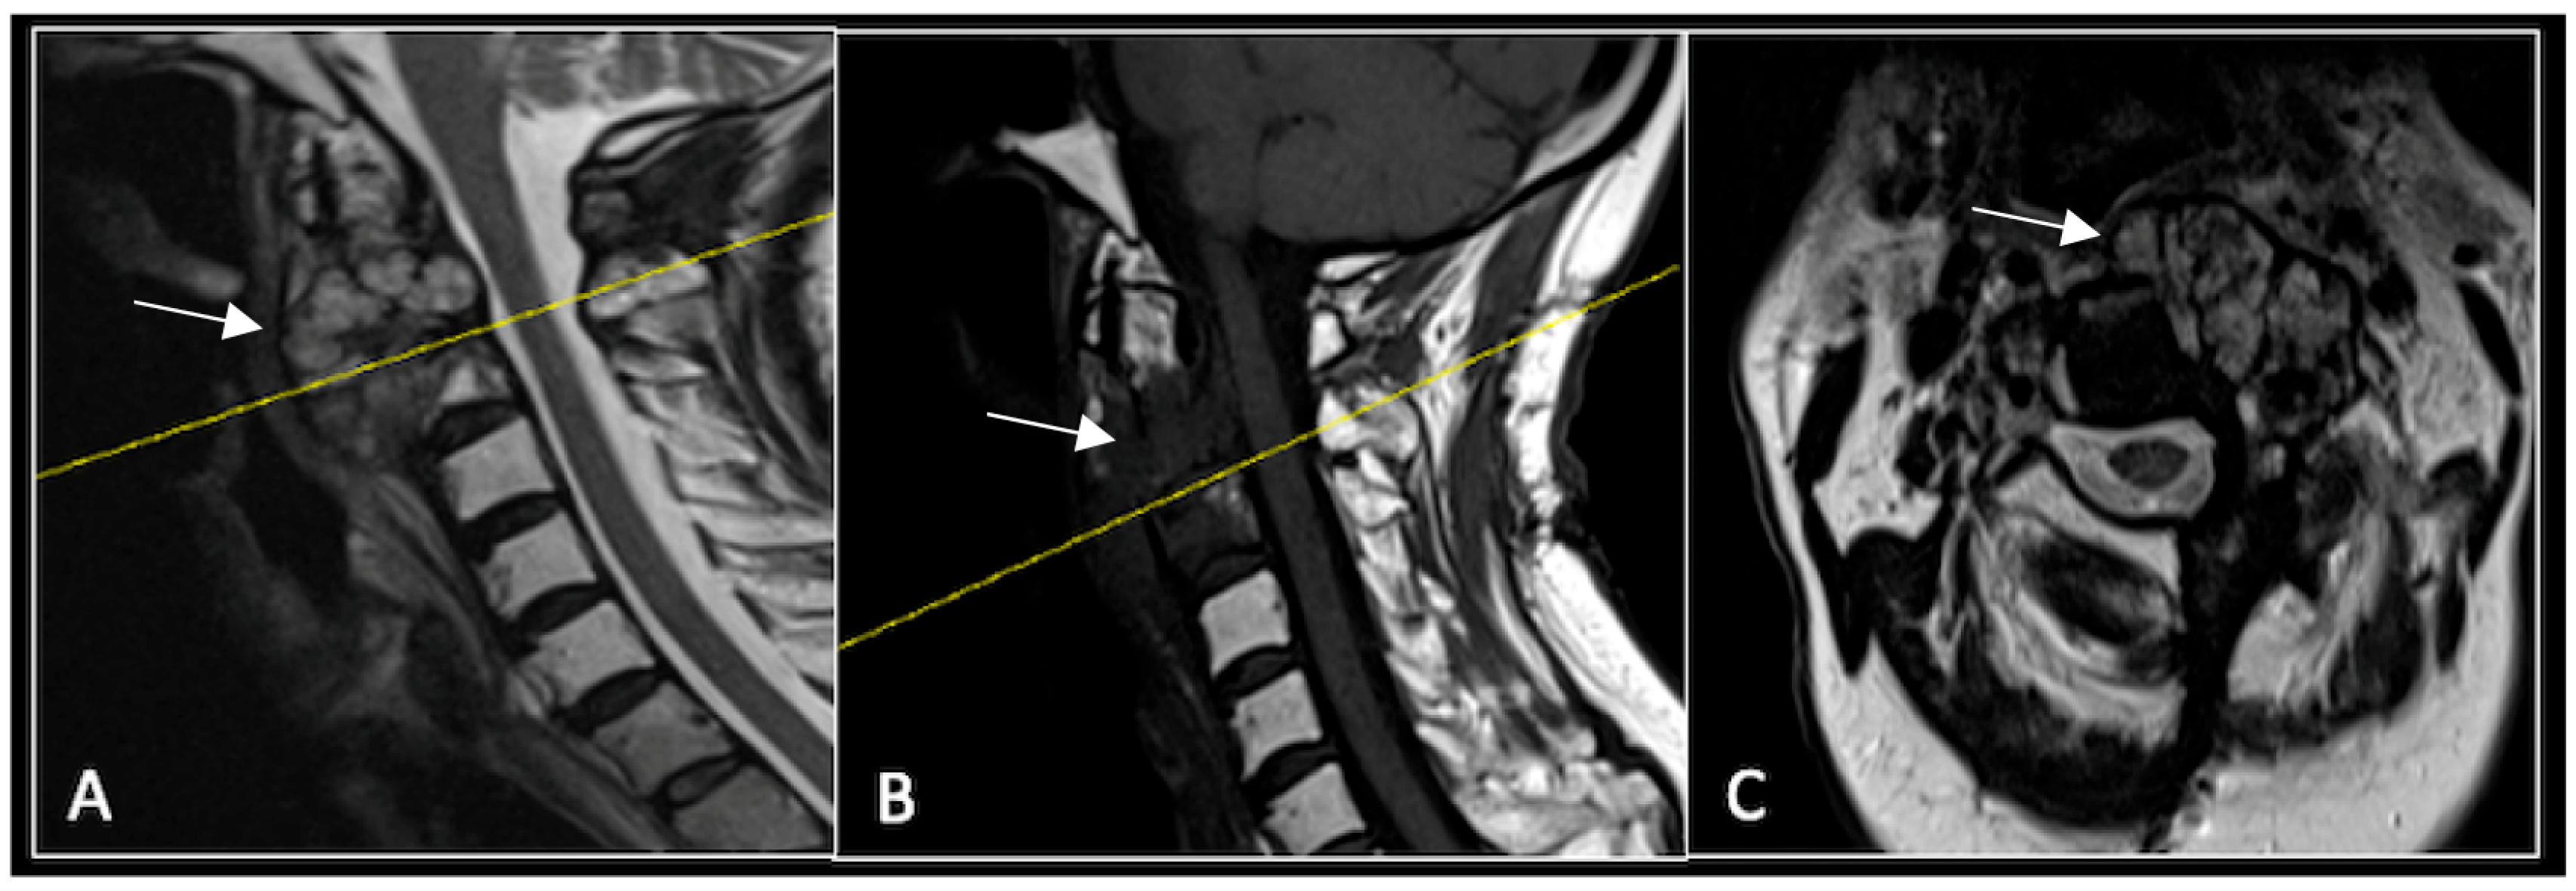

Figure 4.

MRI demonstrating a destructive lobular sacral mass (arrow) with invasion of the S1 vertebral body and complete compression of the cauda equina neural elements. The yellow line on the axial image represents the plane of the corresponding axial section. (A) T2W sagittal; (B) T1W sagittal; (C) T2W axial.

Figure 5.

MRI imaging following separation surgery. (A) T2W sagittal; (B) T1W sagittal; (C) T2W axial. Imaging shows removal of posterior lumbosacral elements with residual disease (arrow) within the S1 vertebral body but significant reduction in tumour dimensions. The yellow line on the sagittal images indicates the level at which the axial image was obtained.